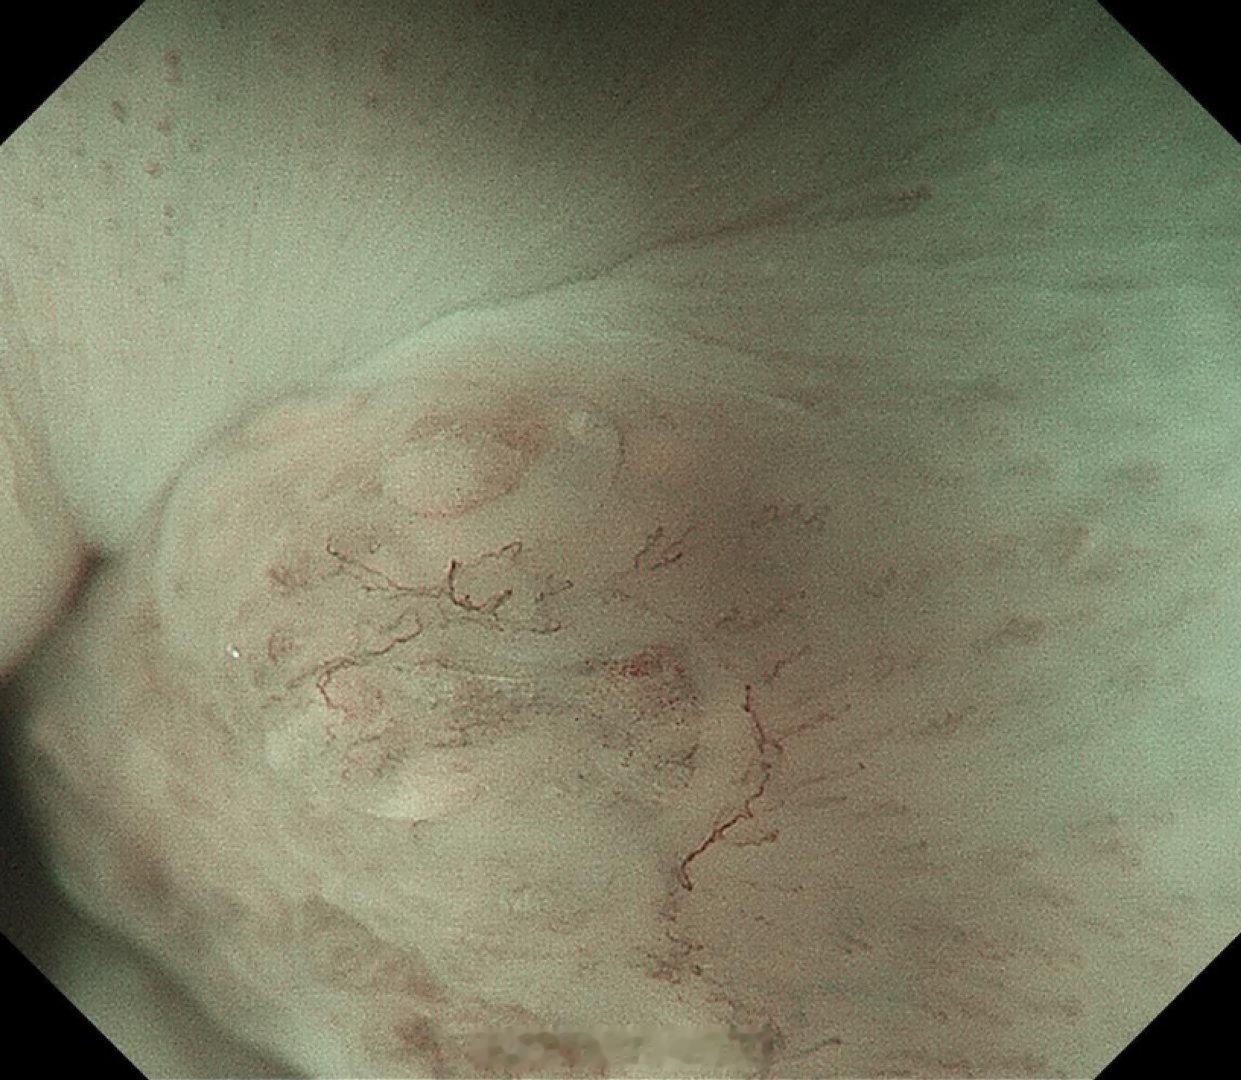

这是个兄弟医院做的内镜发现有贲门病灶,老人体型腹型肥胖很典型,返流持续那么多年导致的Barrett食管癌风险肯定是最高的,她女婿找我精查会诊了一次,我看着病灶虽小,但是有点僵硬,感觉已经到了黏膜下的barrett食管癌,但是他们都想尝试切除看看浸润深度,诊断性esd实施后黏膜下550微米,一般来说这地方超过500微米已经是sm2,淋巴结转移风险急剧加大了,后面就要纠结要不要追加外科手术,但是这个手术做了生活质量会相当不好。所以这种癌的最好措施是预防,发现非常困难,往往一发现就是深了。腹型肥胖的人群减重以减少返流是很重要的。